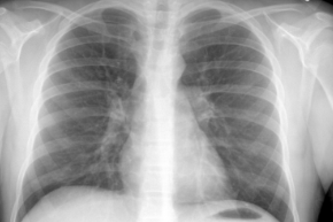

Respiratory disease predictor using breathing analysis and signal processing techniques